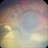

- pediatic retina, vascular anomaly

- Maria A. Martinez-Castellanos. Asociacion para Evitar la Ceguera en Mexico

- Imaging device

- RetCam II

- Fundus photograph of a 3-year-old boy with low vision, esotropia and leukocoria.